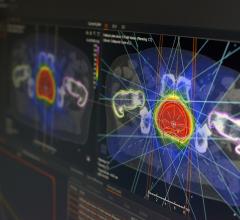

December 11, 2008 - The first patient to be treated clinically with a new treatment planning system for proton radiation therapy developed by RaySearch took place at Uppsala University Hospital in Sweden.

The system is integrated in the Oncentra MasterPlan treatment planning system from RaySearch's partner Nucletron. The University Hospital treats more than 100 cancer patients annually with proton therapy at the The Svedberg Laboratory and the system will be used for all proton treatments in the future.

"The new treatment planning system saves substantial time with its user-friendly tools providing us with various optimization alternatives and the possibilities of making fine adjustments. The dose calculations are exact and optimized to the clinical reality. In addition to the concise presentation of treatment plan data, filter and field shapes are visualized graphically in a clear and pleasant manner," said Christina Vallhagen Dahlgren, senior hospital physicist, proton therapy at the University Hospital.